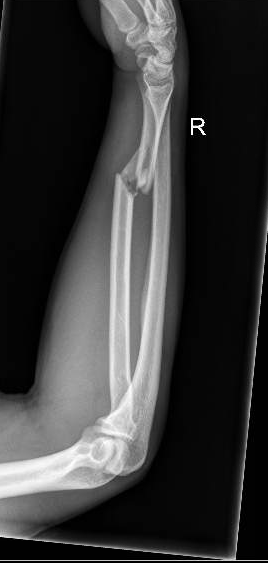

Galeazzi Fracture Lateral XRay JETem 2017